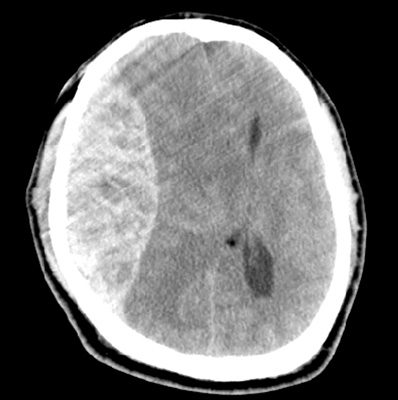

[ 外傷性頭蓋内出血 ]

頭部外傷により生じた頭蓋内出血は外傷性頭蓋内出血と総称され、出血の部位によって硬膜外血腫、硬膜下血腫、くも膜下出血、脳内出血(脳挫傷含む)に分類されます。

血腫によって脳が強い圧迫を受けて、そのために意識の状態が悪いと判断された場合、または悪くなると予想された場合は、血腫を取り除く手術を行います。ただ、手術を必要とするほどの頭蓋内出血は、予定通りに手術が終えられても術後に意識が戻らなかったり、重篤な後遺症が残ってしまうことを多く経験します。特に血をサラサラにする薬を飲んでおられる方や肝臓の機能が特に悪い方は自然止血が得られにくく、極めて予後不良です。

手術は全身麻酔下での開頭血腫除去術を行います。血腫を取り除いた後は、脳が全体的に浮腫んでくることが多いため、腫れてきた脳の圧を逃がす目的で骨を外して皮膚だけ閉じてくることもあります(外減圧術)。外した骨は清潔な状態で冷凍保存し、脳の腫れが落ち着いたところで元の位置に戻す手術を行います(頭蓋形成術)。